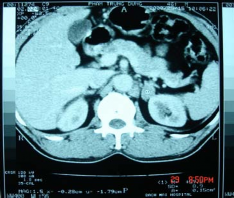

Hình 3.5: U vỏ không chế tiết; Bệnh nhân số 76

Hình 3.6: Pheochrmocytome

đè đẩy tạng; Bệnh nhân số 12